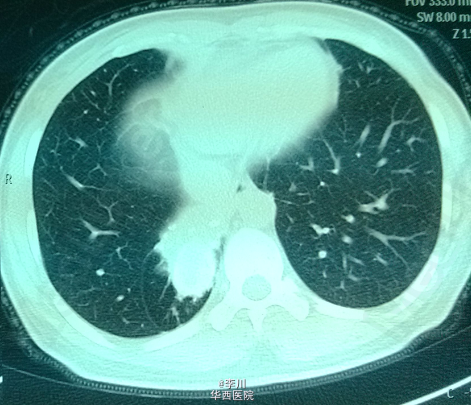

患者为43岁女性,因“咳嗽咳痰伴胸闷、气紧4+月”入院。患者4+月前无明显诱因出现咳嗽咳痰,伴胸闷气紧,外院行相关检查后诊断为“肺炎”,予抗感染治疗20天后无明显缓解。遂于我院就诊。

查体:双侧锁骨上淋巴结未触及肿大。视:双侧胸廓对称,未见畸形,双肺呼吸动度对称。触:触觉语颤对称,未触及胸膜摩擦感,心尖搏动位于左锁骨中线,未见异常搏动。叩:双肺叩清音,双肺活动度对称。听:右下肺肺呼吸音低,未闻及干湿罗音及胸膜摩擦音,心前区未及病理性杂音。我院胸部CT示:右肺下叶不规则片团影,伴右肺下叶不张。

术前诊断为右下肺结核球。于全麻下行右肺下叶切除术。术中取出病灶,可见干酪样坏死。术后病理确诊为肺结核病灶。术后患者恢复可,仍需抗痨治疗。